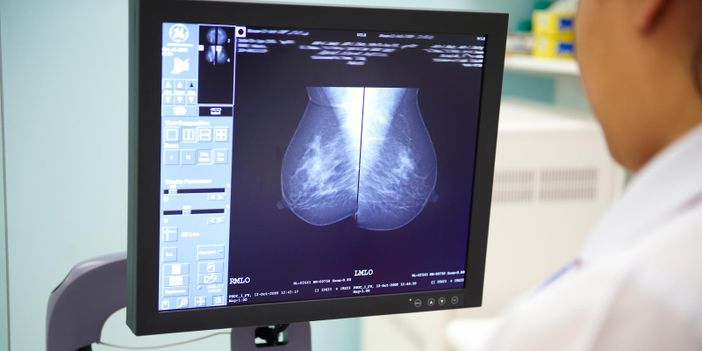

Nell'ambito della collaborazione, Health Triage utilizzerà i dati Optimam per addestrare modelli di deep learning che identificheranno automaticamente le mammografie senza segni di cancro. Questa scrematura delle mammografie con alta probabilità di negatività ridurrà il carico di lavoro dei radiologi, consentendo loro di concentrarsi inizialmente sui casi sospetti e ad alto rischio.

Dato che circa il 99,1% delle mammografie di screening nel Regno Unito restituiscono un risultato negativo e considerando la carenza di radiologi in molti Paesi, l'uso di soluzioni basate sull'IA ha il potenziale di ridurre l'uso delle risorse sanitarie e ottimizzare i flussi di lavoro in radiologia, mantenendo al contempo i tassi di rilevamento del cancro al seno.

Optimam è un database centralizzato in continua espansione che contiene circa 7 milioni di immagini mammografiche anonimizzate provenienti da oltre 465.000 clienti, raccolte da diversi centri di screening mammografico del Sistema Sanitario Nazionale (National Health System – NHS) del Regno Unito. Il database OPTIMAM e la raccolta continua delle immagini sono gestiti dal Royal Surrey, con il finanziamento continuo di Cancer Research UK. Per garantire la validazione clinica della soluzione di Health Triage, il Gruppo Italiano Screening Mammografico (GISMa) agirà come ente indipendente responsabile della supervisione scientifica del progetto.